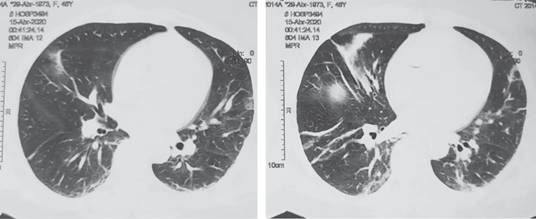

Paciente femenino de 47 años sin antecedentes no patológicos de relevancia. Tabaquismo a razón de 20 cigarros al día con índice tabáquico de 25, el cual se considera riesgo intenso para enfermedad pulmonar obstructiva crónica (EPOC); cesárea electiva hace 13 años. Inicia su padecimiento cuatro días previos a su valoración, al presentar dolor en epigastrio de intensidad 7/10 sin irradiaciones, sin desencadenantes, ni exacerbantes; acompañado de náusea y vómito en cinco ocasiones de contenido gastro-alimentario. A las 24 horas de inicio del cuadro, refiere automedicación e ingesta de butilhioscina 10 mg cada 12 horas, tras lo cual presenta leve mejoría, por lo que deja a libre evolución. A las 48 horas presenta aumento de vómitos, así como migración del dolor hacia fosa iliaca derecha, no refiere fiebre. Acude a particular a las 72 horas de inicio del cuadro, donde se administra tratamiento antibiótico con amikacina, analgésico y metoclopramida a dosis no especificadas, sin ceder el cuadro, por lo que acude a hospital particular al aumentar intensidad de dolor abdominal, en donde se le realizan estudios de laboratorio, los cuales muestran: leucocitosis de 23.3 × 10e3/μl a expensas de neutrófilos (19.48 × 10e3/μl), el resto de resultados de laboratorio sin alteraciones. Del mismo modo, al sospechar cuadro de apendicitis aguda, se solicita TC toraco-abdomino-pélvica contrastada, la cual se reporta con probable apendicitis aguda complicada con absceso localizado, así como hallazgos de broncograma aéreo y datos sugestivos de neumonía atípica por SARS-CoV-2, CO-RADS 4 (Figuras 1 y 2), por lo que deciden envío a urgencias de nuestra unidad.

Figura 2: Tomografía axial computarizada de pulmón, se observan cambios en el parénquima sugestivos de neumonía atípica por SARS-CoV-2.